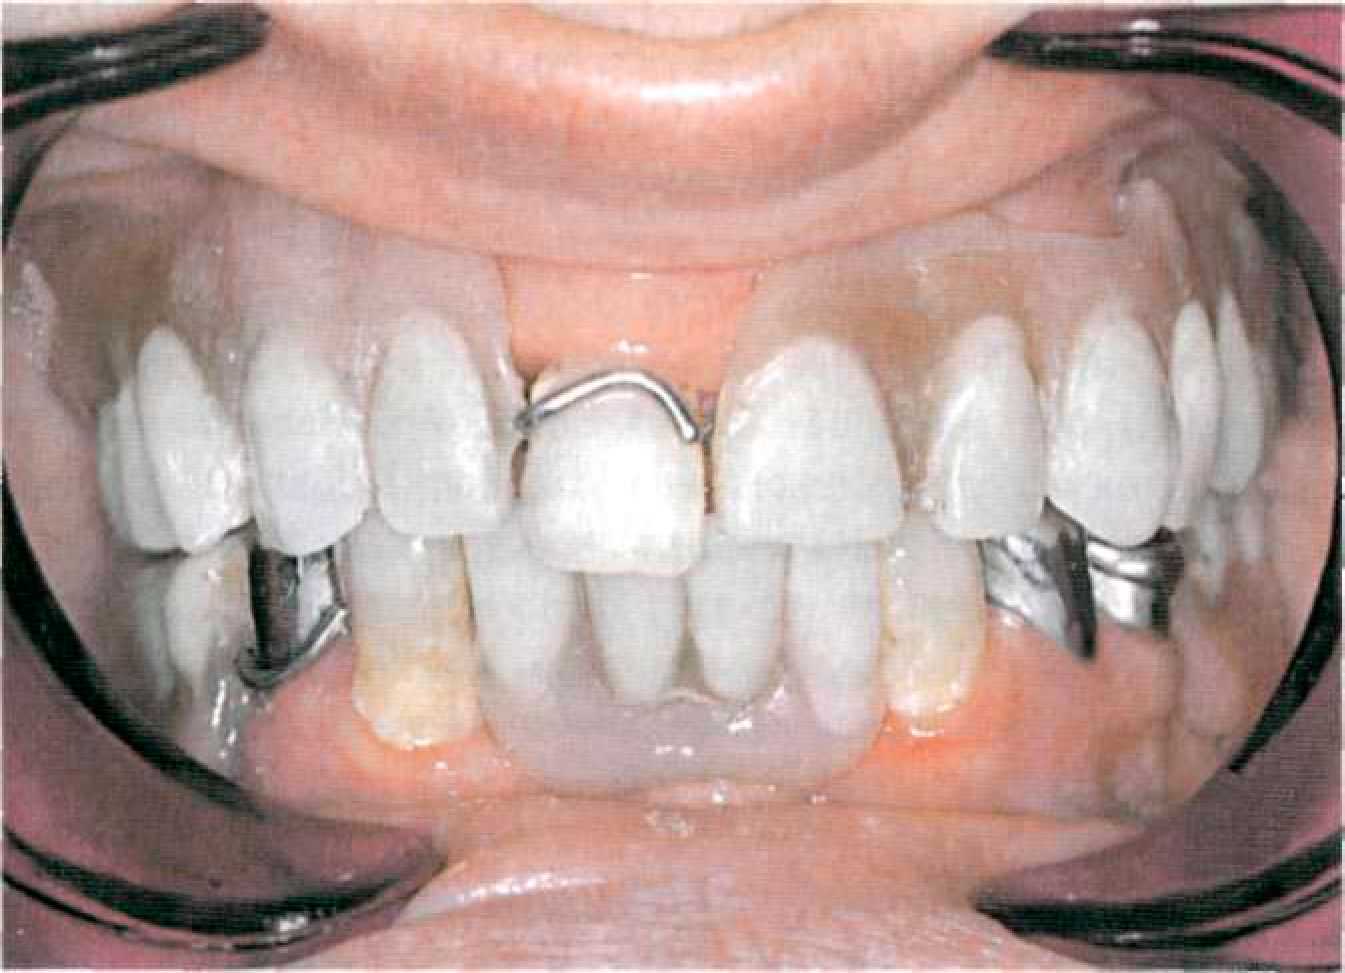

Покрывной протез с телескопическими фиксаторами с фрикционными штифтами Этап 1. После необходимого предварительного обследования, оценки ситуации в полости рта (рис. 127, 128) и санации снимают диагностические оттиски с верхней и нижней челюстей альгинатной массой стандартными ложками, подготавливают диагностические модели из прочного гипса.